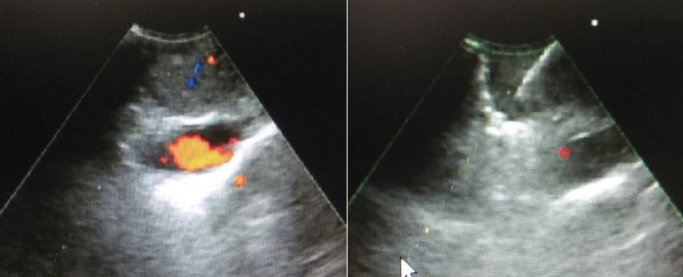

EBUS-TBNA穿刺发现软组织影较浅,在软组织影下方可以看到一条明显的扩张血管,而且为多普勒阳性病例。

图片

患者于放射科行支气管动脉造影,可见右主支气管有畸形血管影。该患者最终行支气管动脉栓塞术。